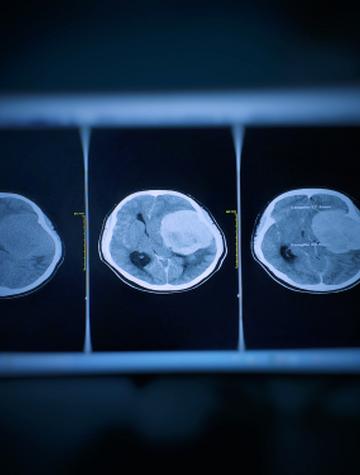

Méningiome : une signature moléculaire pour mieux poser l’indication de radiothérapie

Les méningiomes sont les tumeurs primitives intracrâniennes les plus fréquentes chez l’adulte (40 % des cas). Ils se développent à partir de l’arachnoïde, un des feuillets des leptoméninges, situées à la face interne de la dure-mère. Le risque de développer un méningiome augmente avec l’âge et est deux fois plus élevé chez la femme que chez l’homme. Le traitement repose principalement sur l’exérèse chirurgicale.